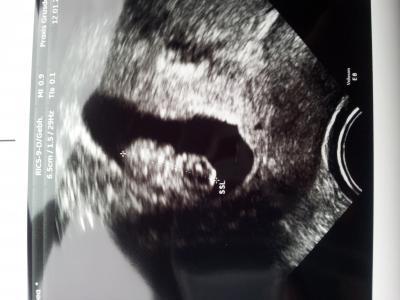

Eigentlich hätte ich morgen meinen Termin gehabt aber durfte auch heute schon kommen :-) Alles ist gut, unser Gummibärchen ist 2,13cm groß und das Herzchen bubbert gleichmäßig < 3 nun dauert es wieder ganze 4 Wochen bis zum Termin

Bild zu 1. offizieller Ultraschall :-) - Forum für August - Mamis